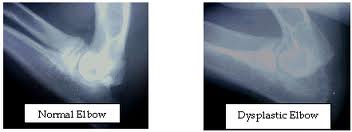

Elbow dysplasia is a general term used to identify an inherited polygenic disease in the elbow of dogs. Three specific etiologies make up this disease and they can occur independently or in conjunction with one another. These etiologies include:

-X-rays are used to evaluate the condition of joint surfaces

-X-rays are used to evaluate the condition of joint surfaces

-X-rays are used to evaluate the condition of joint surfaces